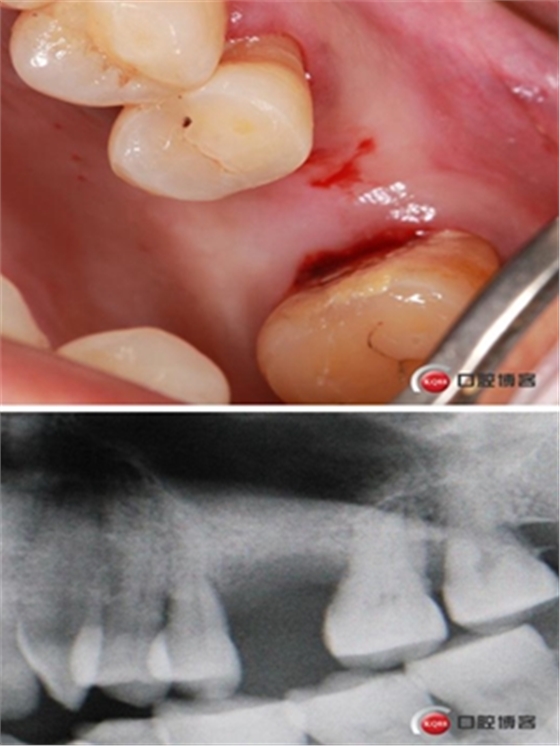

患者女性,58歲,身體健康,無不良咀嚼習(xí)慣,不吸煙、不飲酒。兩年前因左上后牙反復(fù)咬合痛,嚴重影響進食就診,檢查發(fā)現(xiàn)26號牙根尖周炎癥明顯,周圍骨吸收嚴重。拔除患牙,徹底掻刮,由于骨缺損嚴重,沒能即刻種植。6個月后來門診種植。

骨高度僅有3mm,寬度充足。計劃外提升,根據(jù)骨質(zhì)情況決定是否同期植入植體,切開翻瓣,暴露上頜竇頰側(cè)骨壁。